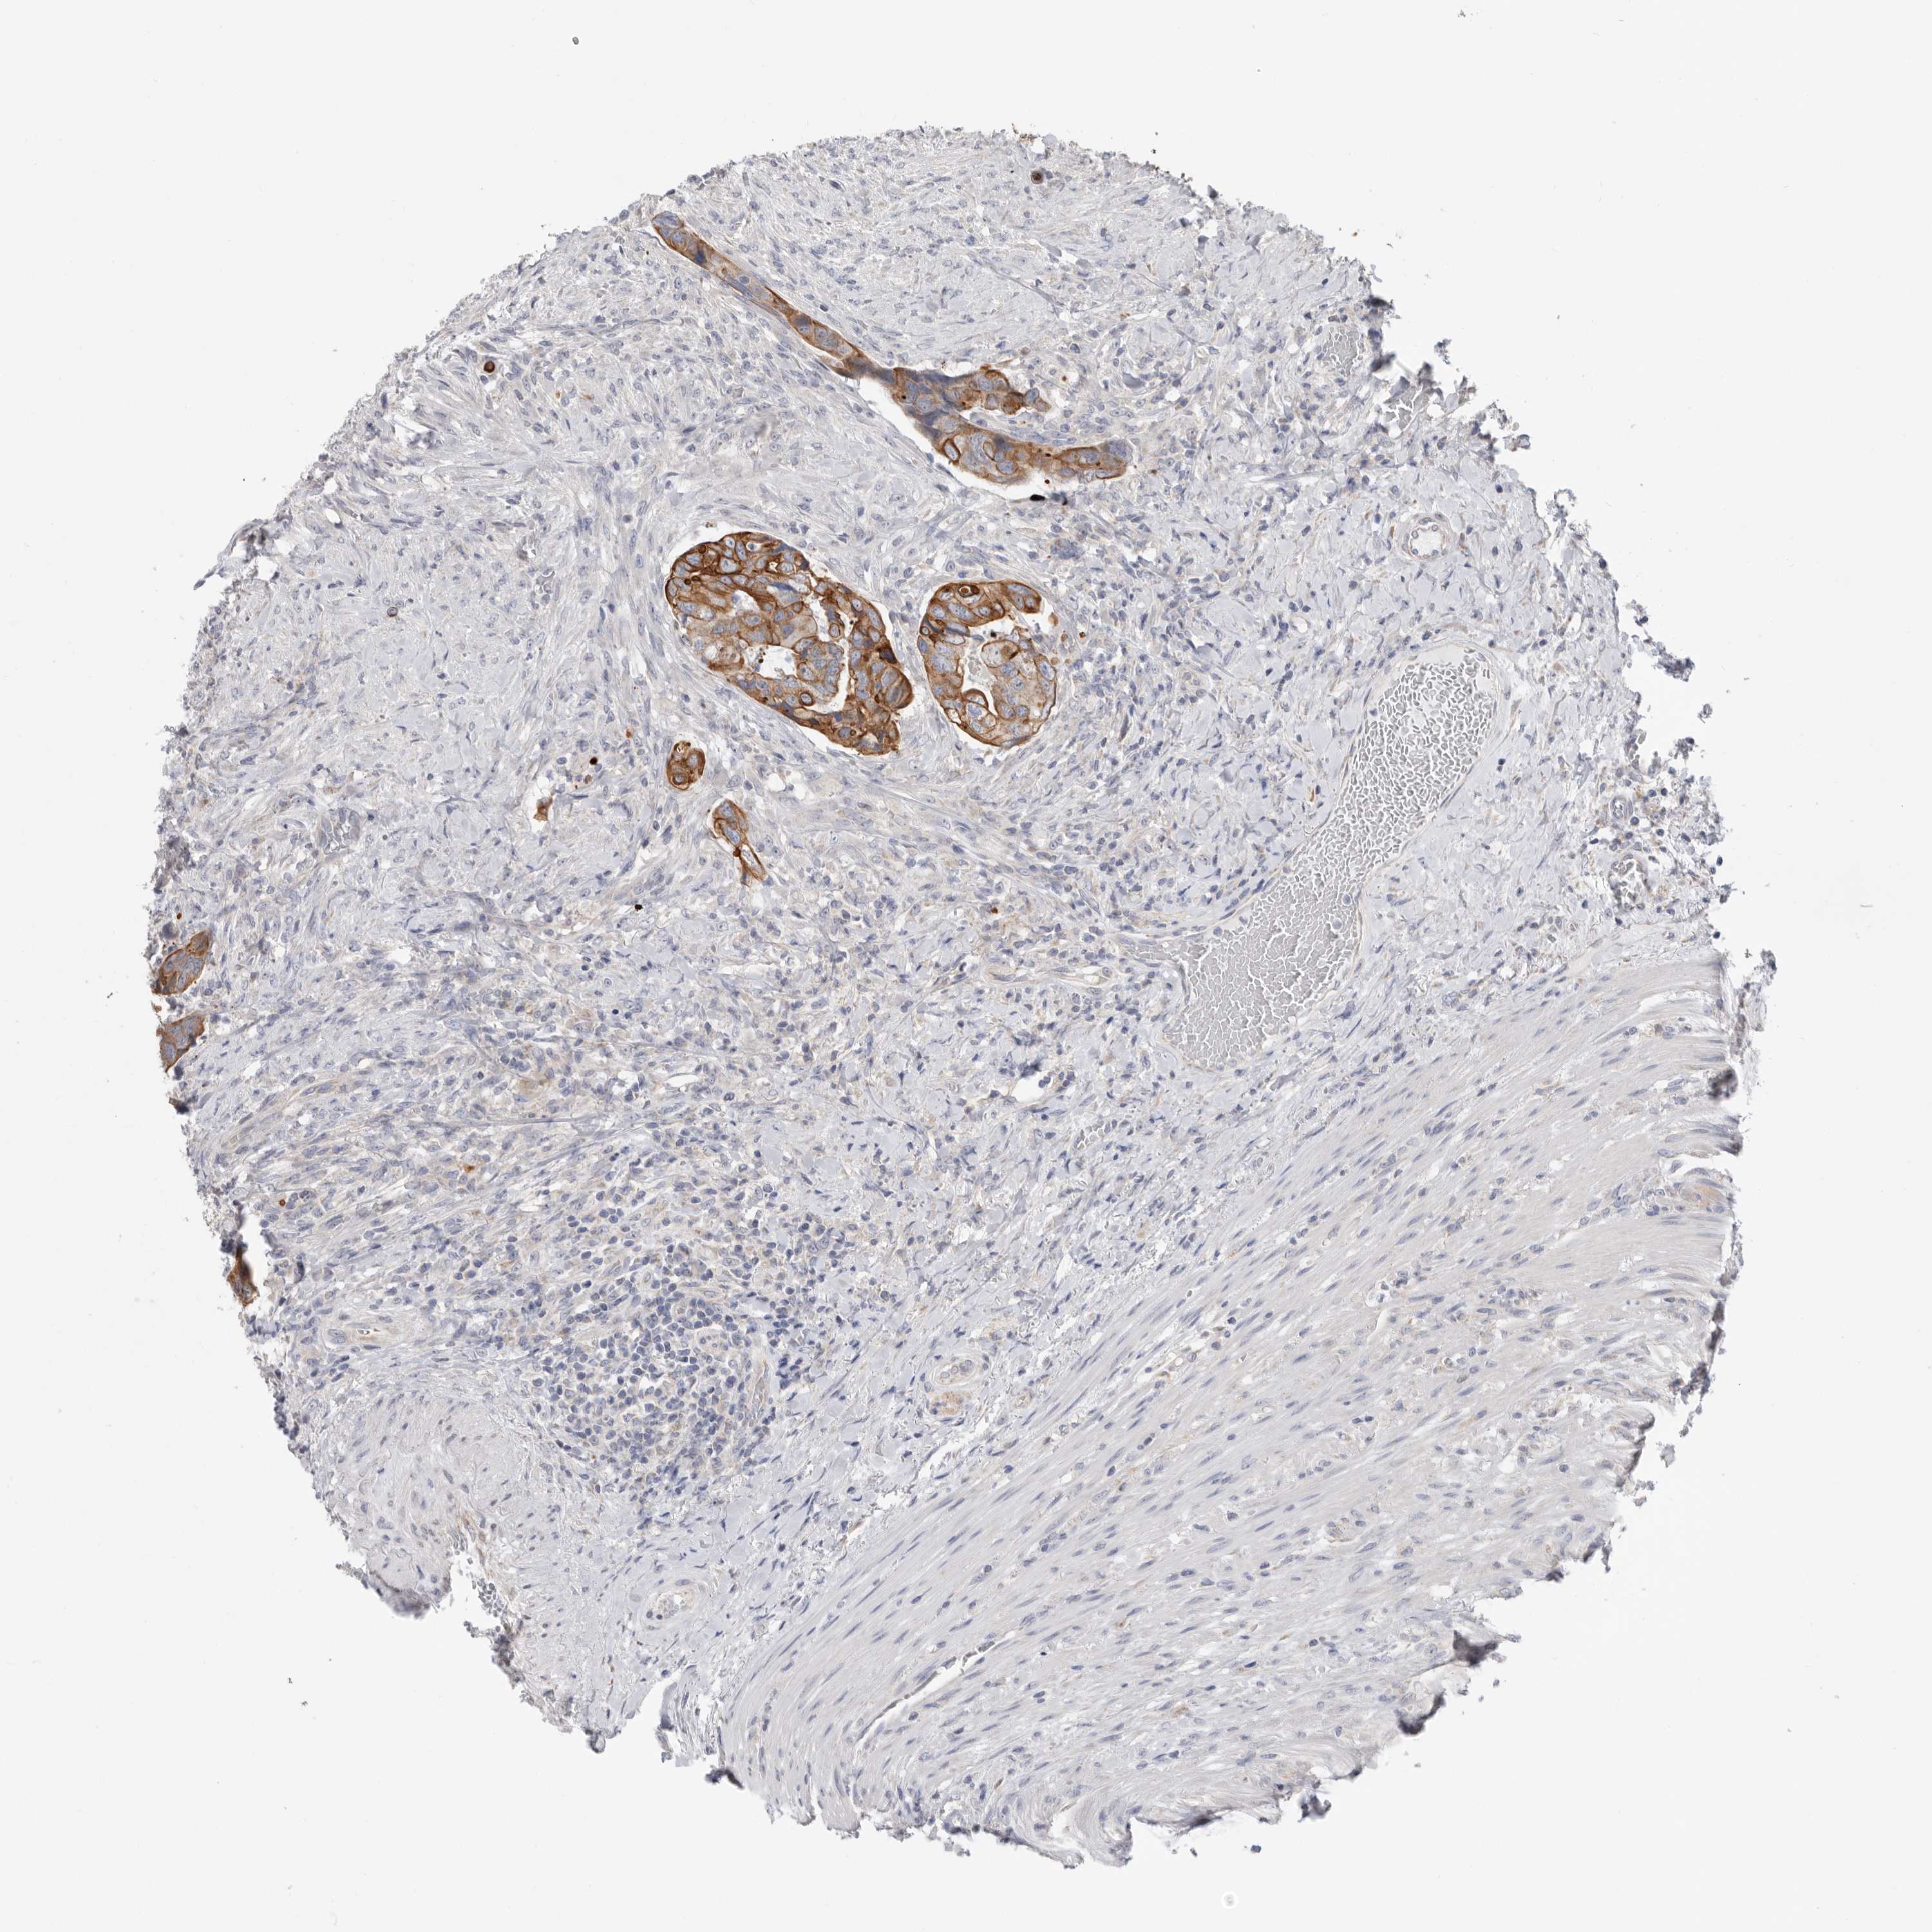

CANCER COLORECTAL CANCER Show tissue menu

Colorectal cancer

Human cancer

Colon adenocarcinoma